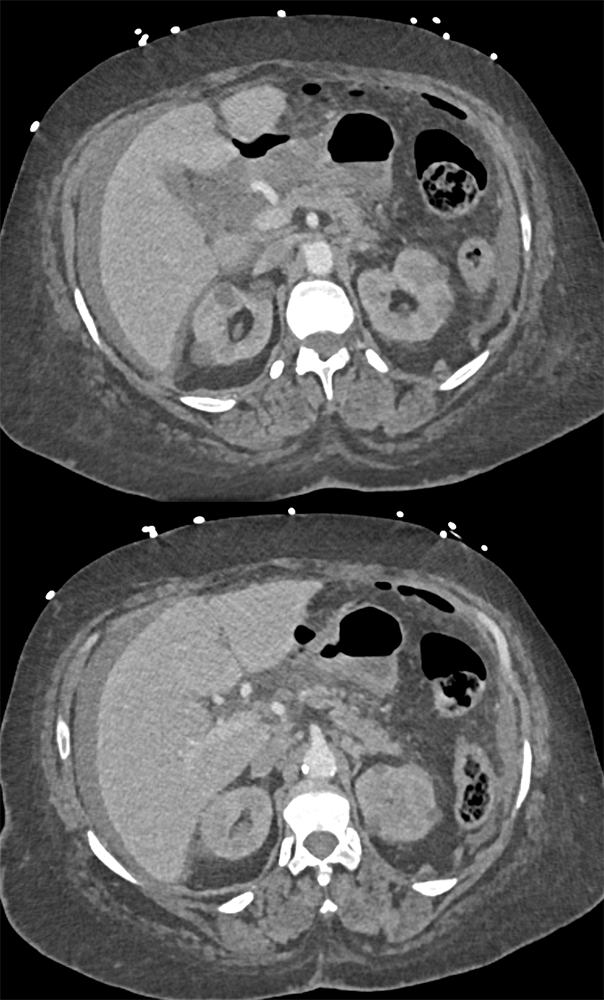

“In our patient, the findings of prominent mucosal folds extending from the pylonic channel on upper gastrointestinal series and the thickened antral wall on CT scans correlate well with the known pathologic appearance of gastnic antral vascular ectasia. Histologically, antral thickening results from a combination of foveolar and fibromuscular hyperplasia. Grossly, the antral fold prominence appears to result from bunching of the mucosa in the thickened, hypercontractile antrum.” Gastric antral vascular ectasia ("watermelon stomach"): radiologic findings. Urban BA, Jones B, Fishman EK, Kern SE, Ravich WJ. Radiology. 1991 Feb;178(2):517-8. |

“Gastric antral vascular ectasia primanily affects women (9:1 female-to-male ratio) aged 56-76 years, and is associated with liver cirrhosis (37%) and achlorhydnia (35%). The usual symptoms are iron-deficiency anemia and melena due to chronic gastrointestinal bleeding from the dilated, superficial, and easily traumatized vessels. Antrectomy is curative, but endoscopic treatment with heat probes or lasers has shown promise.” Gastric antral vascular ectasia ("watermelon stomach"): radiologic findings. Urban BA, Jones B, Fishman EK, Kern SE, Ravich WJ. Radiology. 1991 Feb;178(2):517-8. |